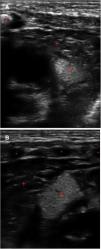

Presentamos un neonato a término en el que se realizó una ecografía torácica a pie de cama por dificultad respiratoria. El plano transversal mediante sonda lineal permite descartar neumotórax2, y, en este paciente, reveló varias imágenes hiperecogénicas bien delimitadas de hasta 2cm limitadas al miocardio (fig. 1, Supl). El parénquima pulmonar presentó un patrón intersticial con gradiente y línea pleural fina con deslizamiento, compatible con taquipnea transitoria (soporte respiratorio durante 48 h). La ecocardiografía corroboró el diagnóstico de túberes cardiacos y la resonancia magnética craneal evidenció túberes y nódulos subependimarios (criterios mayores), líneas de migración radial, nódulos subependimarios y quistes en la sustancia blanca (fig. 2) que, junto con el estudio genético, diagnosticaron al paciente de esclerosis tuberosa tipo II de Bourneville (gen TSC2).

. RM de cráneo a los 6 ddv con secuencias TSE T2 axial A y B), T1 IR axial C y D) T13D coronal E), T13D sagital F), TSE T2 sagital G) y T13D sagital tras la administración de contraste intravenosos sagital H). Se observan tubers corticales hipointensos en T2 e hiperintensos en T1 –flechas amarillas en A y C)–, líneas de migración radial en la sustancia blanca –flechas azules en A, C y F)–, nódulos subependimarios –flechas rojas en B, D, E y F)– y quistes en la sustancia blanca que se muestran hiperintensos en T2 sin realce tras la administración de contraste –círculo verde en G y H)–. El color de las figuras solo puede apreciarse en la versión electrónica.